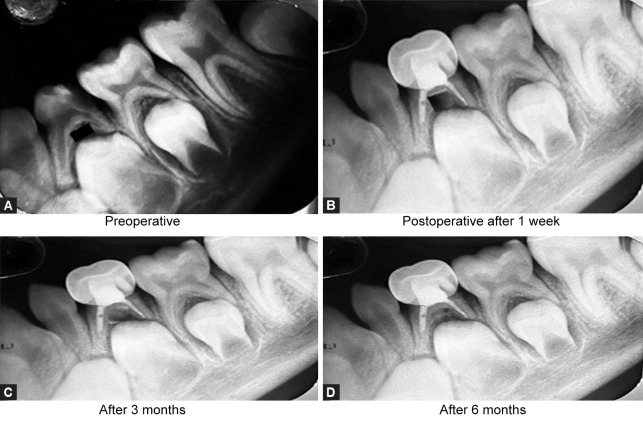

Materials and methods: The present study was conducted in 60 children of age group 4-10 years requiring multiple visit pulpectomy for their primary molars. Selected teeth were randomly divided into three groups: group I - calcium hydroxide with Ocimum sanctum, group II - calcium hydroxide with Curcuma longa, and group III - calcium hydroxide with Aloe barbadensis miller. Clinical and radiographic evaluation was done among the groups at intervals of 1 week, 3 months, and 6 months.

Results: There was no significant difference in the clinical and radiographic success rate among the groups.

Conclusion: Among the three groups, calcium hydroxide with Ocimum sanctum group showed a higher success rate and that with Aloe barbadensis miller group showed the least success rate.